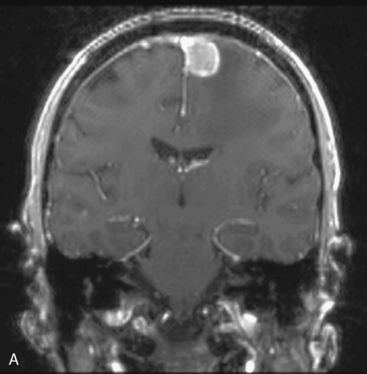

矢状窦旁是 脑膜瘤 生长较常见的部位之一,占全部颅内脑膜瘤的18-23%。矢状窦旁脑膜瘤(PMs)与上矢状窦及引流静脉的紧密联系,使根治性切除难以实现,可能导致神经功能的持续损害,...

Cushing和Eisenhardt将矢状窦旁脑膜瘤定义为肿瘤充填矢状窦旁角,在肿瘤和上矢状窦间无脑组织。对此,国外也有相关的研究数据为证:辛普森I级切除5年后的复发率为35%,II级切除为4%,I...

镰旁和矢状旁脑膜瘤是颅底脑膜瘤的常见部位,切除手术可从根本上解除占位效应,但手术不慎也有可能造成并发症...